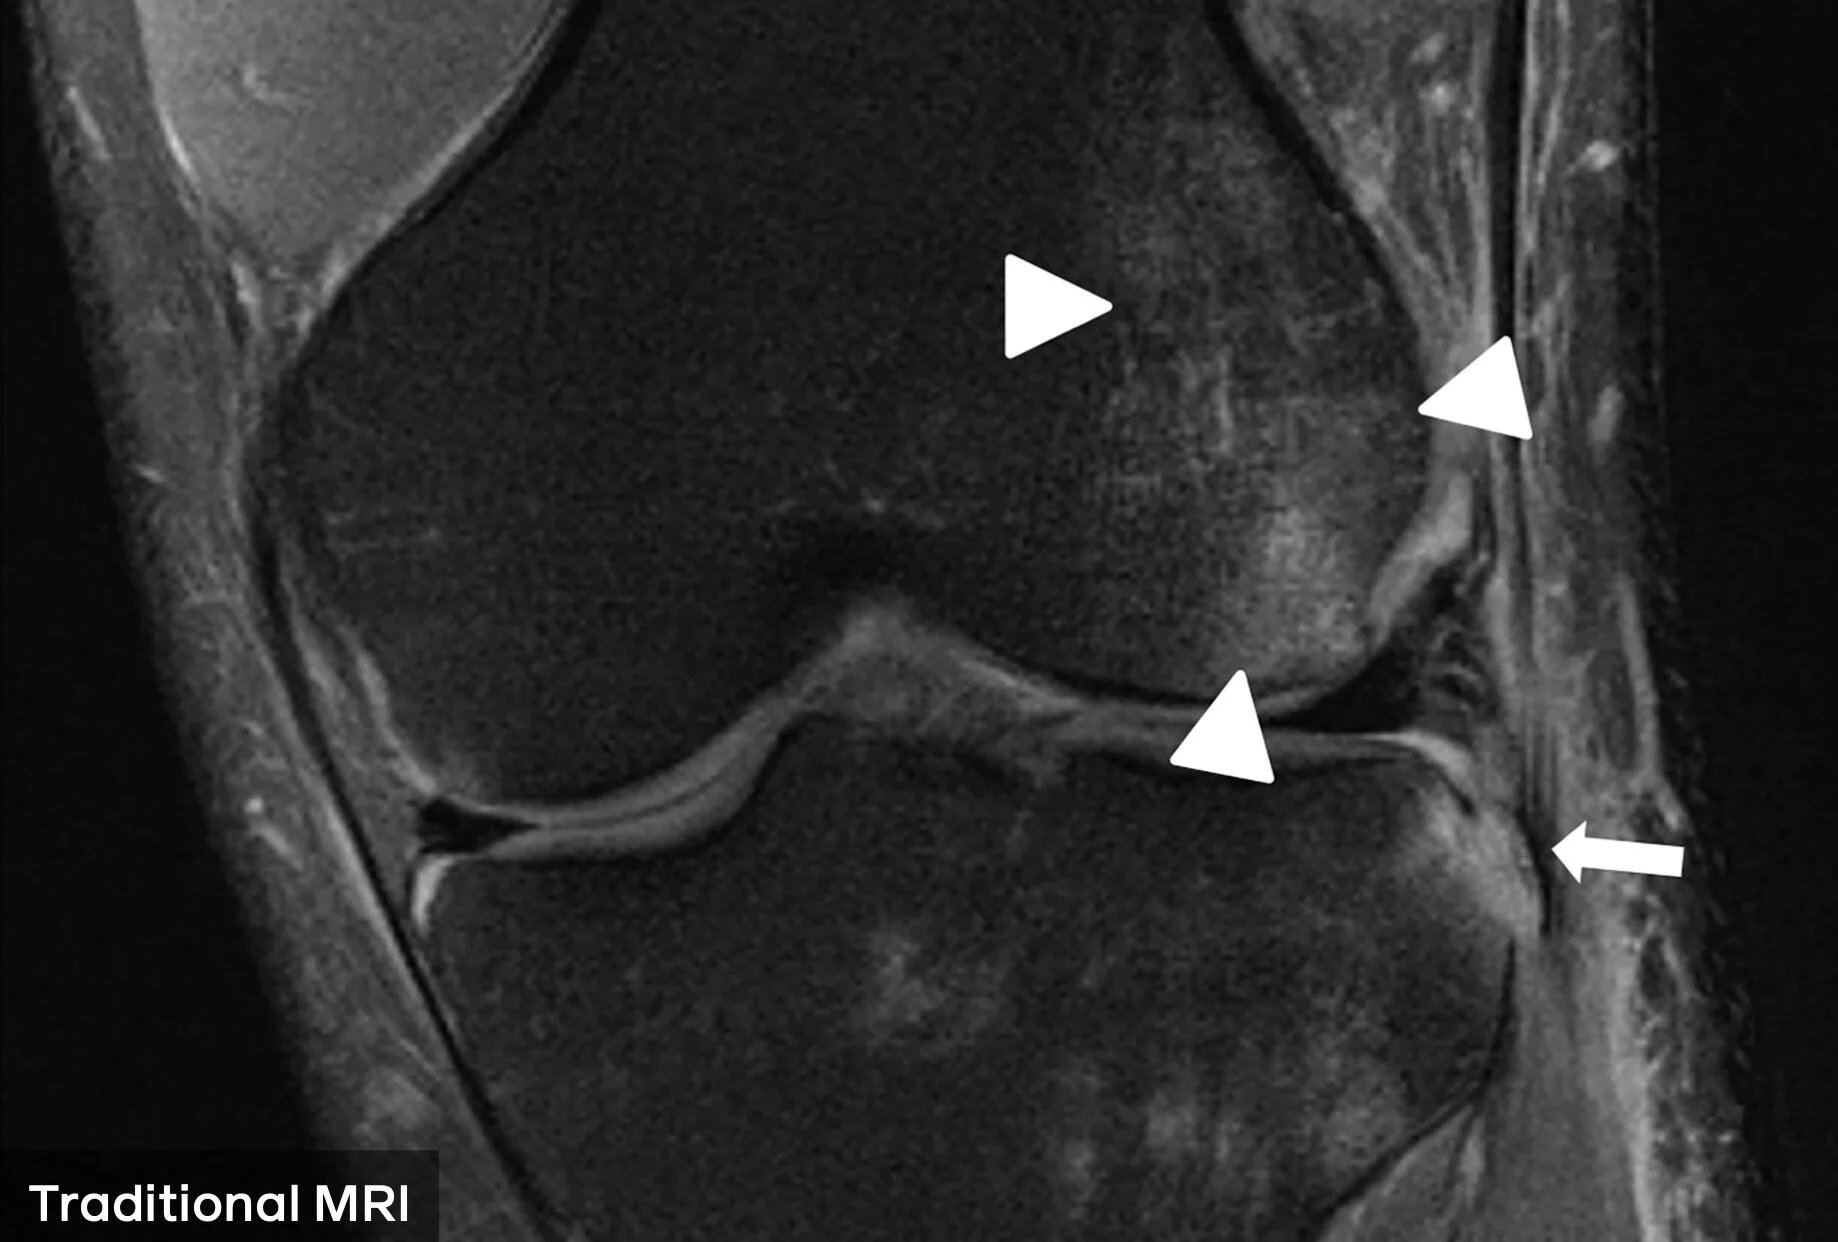

One way of minimizing these unpleasant experiences is by reducing the time spent in the tube, without compromising the thoroughness, quality & accuracy of the scans, because otherwise this would lead to wrong diagnosis. This is where the AI comes. fastMRI is a research project run by Facebook and NYU. The aim is to be able to reproduce accurate scan images with 4x less data using AI image reconstruction technology. By being able to leverage less data, patient has to spend less time. You can read more about how the ML Model works here.

This is how a traditional MRI of a knee looks like Source: FB

Full data was used for a traditional MRI Scan. Source FB

MRI scan result generated by the AI model. Source: FB

4x less raw data used for AI MRI scan. Source: FB